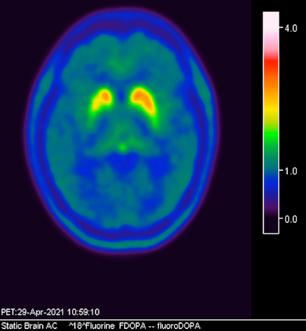

Femenino de 65 años, antecedente de hipertensión arterial de 20 años de evolución en control. Sin antecedentes familiares relevantes de enfermedades neurológicas. Acudió a consulta médica por deterioro progresivo en su capacidad motora y dificultades en las actividades diarias. Desde hace 2 años ha notado cambios en su marcha y en su habilidad para realizar movimientos finos con las manos principalmente del lado izquierdo, rigidez muscular, temblor en reposo siendo mayor del lado izquierdo y dificultad para iniciar y mantener el movimiento, especialmente al levantarse de una silla o al comenzar a caminar. Además, los familiares han observado que tiene una expresión facial inexpresiva y que su voz se ha vuelto más monótona. A la exploración física con expresión facial inexpresiva, temblor de reposo bilateral en manos de predominio izquierdo, rigidez muscular generalizada, más pronunciada en las extremidades superiores, bradicinesia evidente en la realización de movimientos finos de las manos, marcha festinante con pasos cortos y arrastrando los pies, reflejos osteotendinosos normales, no se observan déficits sensoriales. Se realiza adicionalmente la escala de Evaluación de la Enfermedad de Parkinson (UPDRS) con un total de 35 puntos, indicando moderada afectación de la enfermedad. Inicialmente se realiza una tomografía simple de cráneo, sin alteraciones estructurales, al no encontrar algún hallazgo se decide realizar posteriormente Resonancia Magnética Cerebral 1.5 Tesla: sin alteraciones estructurales significativas. Por este motivo y ante la alta sospecha clínica se realiza estudio de imagen molecular PET-RM con 6-[18F] FDOPA en equipo 3 Tesla en el cual se observa la disminución de la captación de la 6-[18F]FDOPA a nivel de putamen y caudado de predominio derecho evidenciando la degeneración dopaminérgica nigro presináptica a este nivel, con un patrón tipo 2 (Egg shaped) así como la mala definición de nigrosoma, estos hallazgos compatibles con enfermedad de parkinson. (Figura 1 y 2)

axial fusionada de PET-RM 3T con

con disminución de la captación del radiotrazador a nivel de ambos putámenes en la región posterior y media de predominio derecho así como disminución en el caudado ipsilateral.

2. Reconstrucción tridimensional avanzada de imagen híbrida PET-RM 3T con 6-[18F]FDOPA observando disminución de la captación del radiotrazador a nivel de ambos putámenes en la región posterior y media así como en el núcleo caudado derecho.

Figura 3. Reconstrucción mediante imagen molecular de imagen híbrida PET-RM 3T con 6-[18F] FDOPA observando disminución de la captación del radiotrazador a nivel de ambos putámenes en la región posterior, media y anterior así como en ambos núcleos ca dados de predominio derecho.

Figura 4. Reconstrucción mediante imagen molecular de imagen híbrida PET-RM 3T con 6-[18F]FDOPA observando captación adecuada y conservada del radiotrazador en el cuerpo estriado (ambos putámenes y núcleos caudados) en un paciente negativo para enfermedad de parkinson.

En cuanto al campo de los estudios de imagen convencional y de laboratorio no existe alguna prueba que pueda confirmar la enfermedad. Sin embargo, las imágenes de diagnóstico por métodos de imagen molecular del tipo no invasivas, como la tomografía por emisión de positrones (PET) en conjunto con un resonador de 3 tesla (RM 3T), pueden respaldar el diagnóstico de un médico, actualmente éste método tiene una sensibilidad diagnóstica de 95.4%, especificidad 100%, valor predictivo positivo del 100% y valor predictivo negativo del 87.5%. (5,6)

La enfermedad de parkinson es una enfermedad neurodegenerativa con afectación principalmente motora (temblor, rigidez y acinesia) de sospecha y diagnóstico clínico, ante la limitación de los estudios de laboratorio y métodos de imagen convencional para el diagnóstico toman gran relevancia las técnicas de imagen molecular no invasivas como el PET-RM y PET-CT con 6-[18F]FDOPA que cuentan con gran sensibilidad y especificidad para respaldar o descartar el diagnóstico médico ante la sospecha de la enfermedad de parkinson y algunas otras enfermedades del trastorno del movimiento.